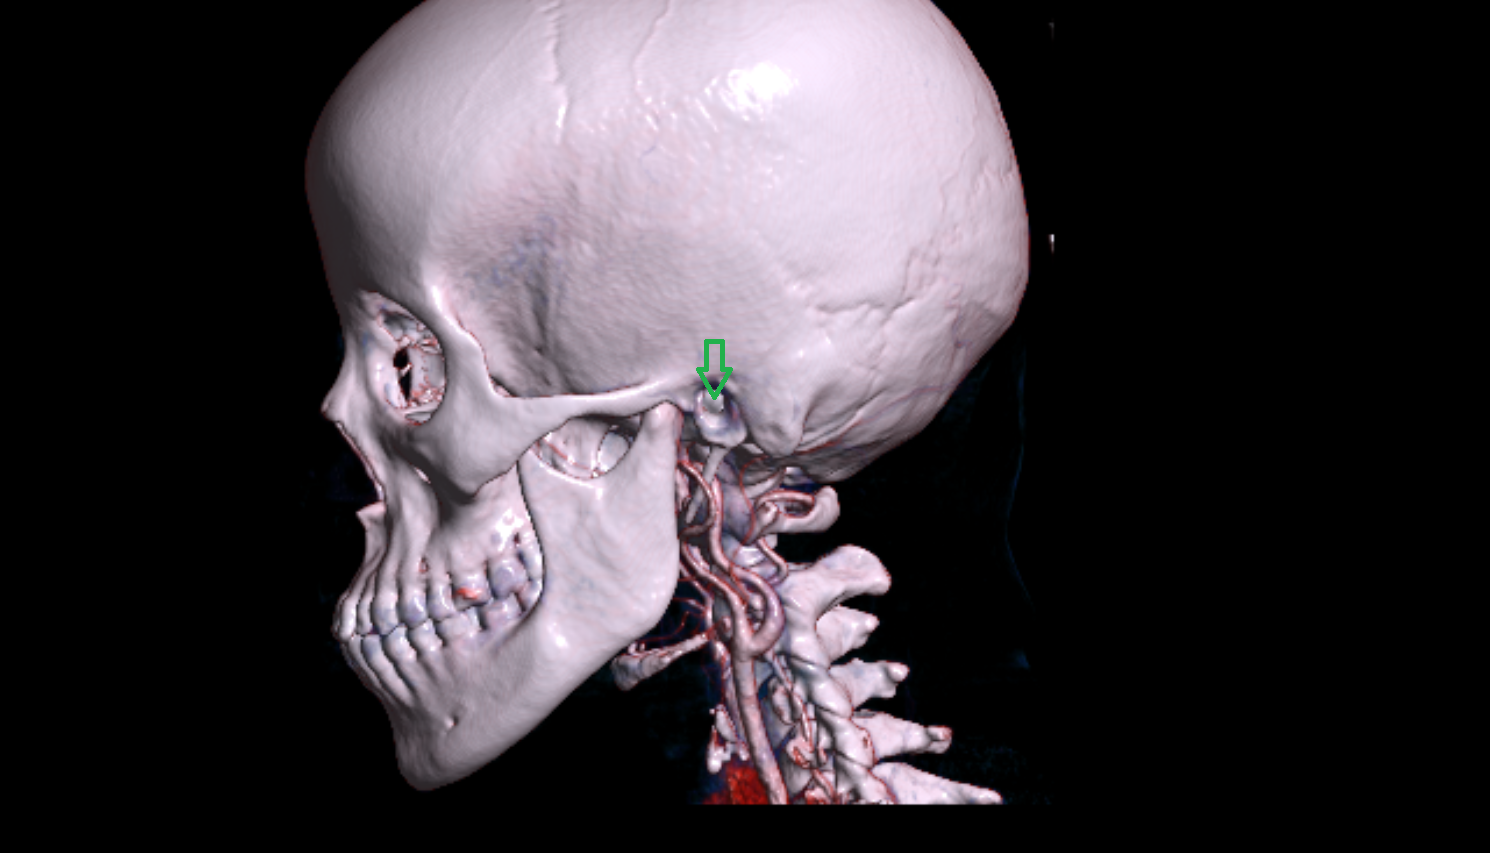

- Carotid bifurcation

- Internal carotid artery (cervical part)

- Internal carotid artery (petrous part)

- Carotid canal